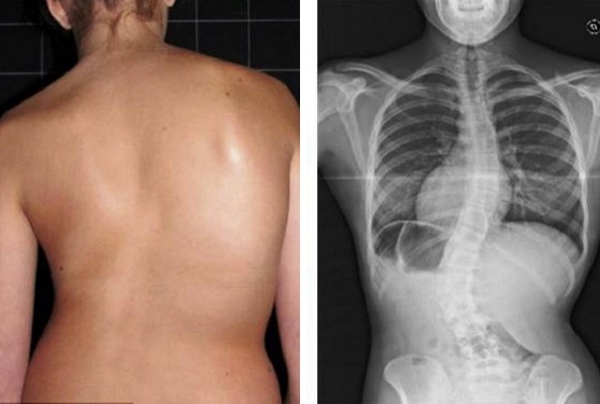

Všechny klouby vyžadují pozornost, ale hlavní je páteř. Postarejte se o ni, dřív než začnou nevratné změny. Podívejte se, co čeká ty, kdo ignorovali signály organismu: KÝLA, POSUN OBRATLŮ, DEFORMACE PÁTEŘE, ZHRBENÍ, ÚPLNÁ ZTRÁTA POHYBU. Nečekejte na okamžik, kdy i jednoduchý pohyb bude mučením!

Podívejte se na tyto fotografie. To se stalo těm, kdo příznaky ignorovali. Dnes jsou bezmocní a mnoho z nich nemá na koho se o péči spolehnout. Opravdu chcete takový osud?

Tento produkt mě zachránil před kyfózou a bolestmi zad! Sedavá práce a osteochondróza jsou nesnesitelné a lékaři krčili rameny, aleCORDYCEPS PULSE

mě opravdu zachránil bez přehánění. Kyfóza i deformace páteře jsou

něco opravdu tvrdého! Raději to sledujte. Tady je můj výsledek: